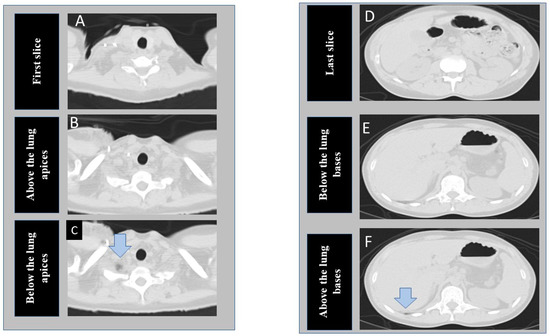

The segmentation tool is comparable to a semantic segmentation neural network (such as UNet) and is used for segmentation and detection of specific findings in images. Figure 1 shows the transverse chest CT images at the different section of the lung selected for model development.

At the time of writing this manuscript, the software is able to process a limited number of 2D images per patient as input, so we elected to train two different models on instances near the lung apices and bases (three images each at lung apices and bases) instead of including every instance in the CT series. At the apex, we de-identified and exported three images, including the cranial-most image (first image), an image just above the lung apices, and an image just below the lung apices (including a portion of lung apex/apices). Likewise, at the base from the same CT examinations, we exported three additional images, including the last, caudal-most image, an image just below the lung base, and an image including the lung base. Thus, for each CT, we exported and labeled six images from each CT examination included in our study (R3-5). Images just above the apex and just below the lung base represented the anatomic location of “optimal” scan coverage. Images below the apex and/or above the lung bases represented “incomplete” scan coverage. Finally, the first and last images represented “over-scanned” anatomy when these were >2.5 cm beyond the lung apices or bases. We recorded the distance between the first image and the image just above the lung apex (cranial distance) as well as the distance between the last image and the image just below the lung base (caudal distance).

Figure 1. Transverse CT images at the superior (AC) and inferior (DF) scan locations of a chest CT examination. The first column shows the cranial-most (first image A), perfect scan (B), and under-scanned (C) image locations at the lung apex. The second column of images represent caudal most image (last image D), perfect scan location at lung base (E), and missed lung basilar anatomy (F). (The arrows point to tiny portions of lung parenchyma).